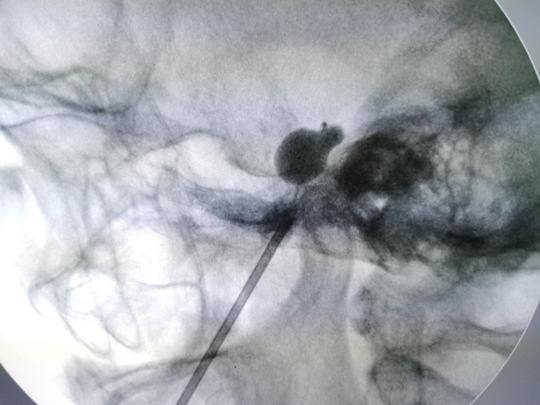

三叉神经颅底穿支的解剖结构复杂,颈内动脉等重要血管毗邻仅1厘米,穿刺路径中一旦有误,大血管受损,就会出现致命的大出血等严重并发症。手术紧张中进行着。预先设计穿刺通路后,在机器人引导下,首先使用穿刺针穿刺卵圆孔,将目标容量只有0.7毫升左右的微球囊经过卵圆孔置入麦克氏囊内,随后慢慢扩张微球囊,通过术中动态影像扫描检测和修正参数,对三叉神经半月节产生微毁损效应,达到微创治疗三叉神经痛的目的。

三位患者的手术均一针穿刺到位,手术历时30分钟左右。在麻醉科医生的配合下,术中患者各项指标平稳,球囊成像满意。